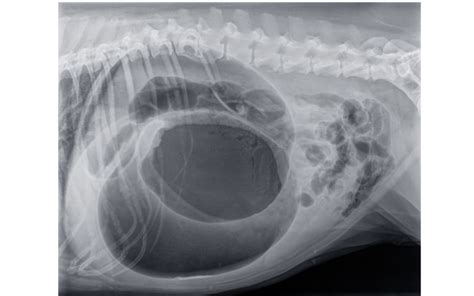

- RTG (Röntgenové vyšetrenie): RTG hrudníka sa používa na zobrazenie veľkosti a tvaru srdca, ako aj na detekciu prípadných zmien v pľúcach (napr. pľúcny edém). Tento postup môže poskytnúť informácie o veľkosti srdca, polohách chlopní a prítomnosti prípadných pľúcnych komplikácií.